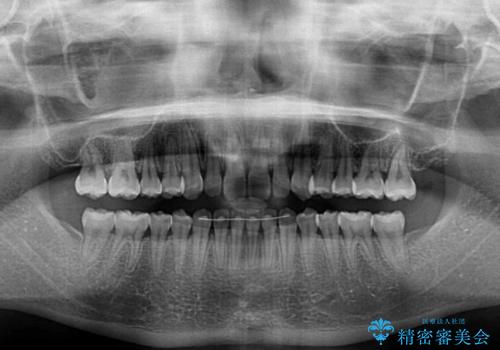

海外勤務中でも矯正治療 インビザラインによる軽度叢生改善

- 前歯のデコボコを気にして来院された患者様です。

治療期間中に海外勤務になる可能性が高いことが分かっていましたが、矯正治療を始めたいとのことでしたので、インビザラインを用いて治療することとしました。

通常であれば半年から10ヶ月程度で終了する歯並びでしたが、海外に長期出張することになったため、1年10ヶ月の期間を要しました。

出張に行かれてしまうと追加のマウスピースを発注できないため、マウスピースの交換頻度を低くし、一時帰国のタイミングに合わせていくことで、スムーズに進めて行くことができました。